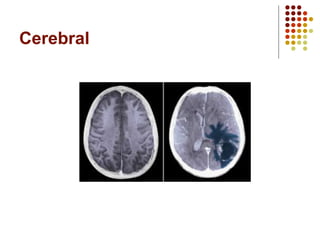

Ejemplos de Tumores

Cerebral